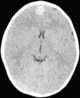

Ossification of falx cerebri